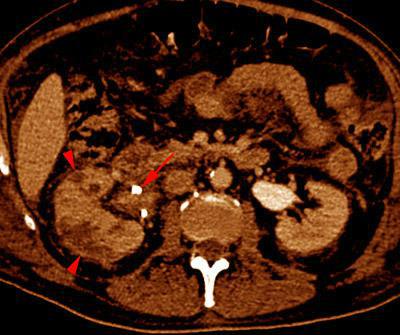

Pielonefritis aguda 2